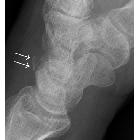

On plain film, dorsal avulsion injuries are best detected on a lateral projection, where typically an avulsed flake of bone is identified lying posteriorly to the triquetral bone (see pooping duck sign). CT or MR may be more sensitive than conventional radiographs for detection of avulsion injuries.